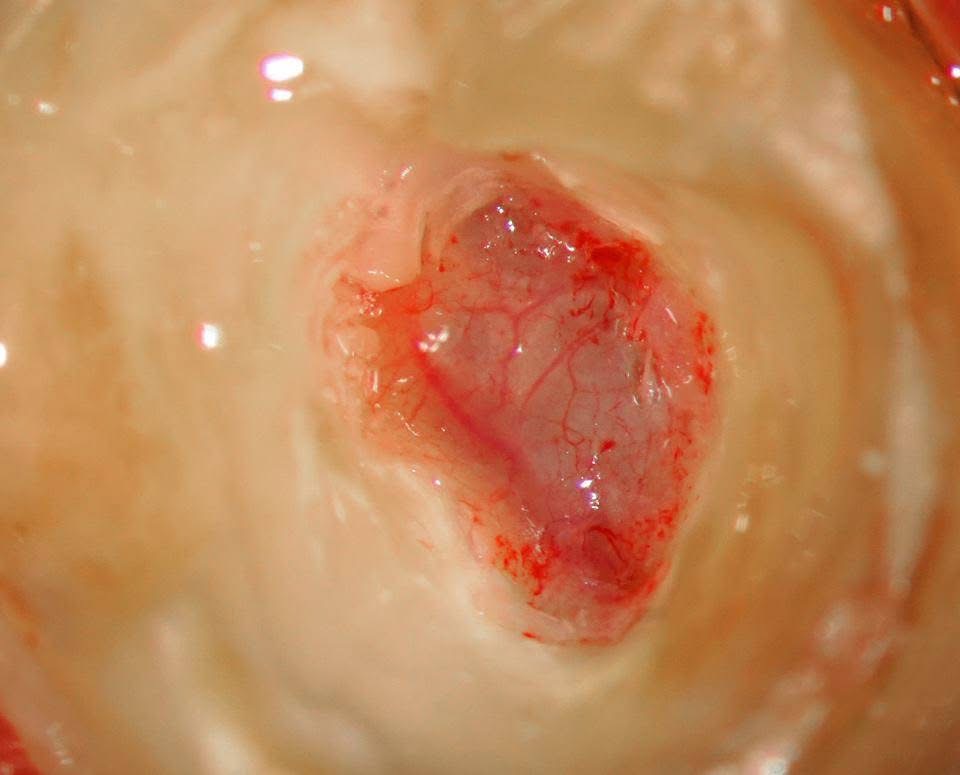

症例1:歯の中の神経が出血して歯髄炎を起こしているケース

歯の中の神経、歯髄が充血しています。

歯髄の状態が出血をしている場合、歯髄炎を起こしている事が多くあります。